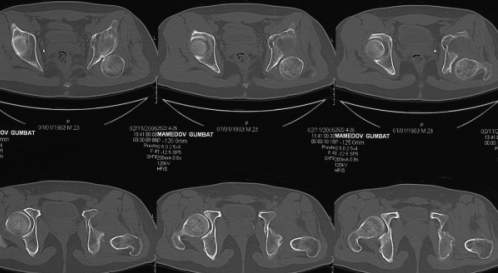

важаемые коллеги,пациент 23 лет (вес 75 кг), обратился к нам по поводу боли в тазобедренном суставе при ходьбе, нестабильность в нем при нагрузке. Ходит с тростью. 8 мес. назад попал в ДТП (никаких медицинских документов у него нет). Стоит ли открываться и вправлять вывих или сразу делать бесцементное тотальное эндопротезирование? С уважением, А. В. Вакуленко Клиника эндопротезирования суставов, г. ДонецкDear All, male patient 23 y.o., body weight 75 kg. Had RTA 8 months ago (medical records unavailable). Now has pain on motion in his left hip. On weight-bearing hip is unstable (patient use cane while walking). Keeping in mind his age, is it worth to perform open reduction? Or just do uncemented THR? Any comments are very welcome.

After 8 months, the hip will not easily come down into the acetabulum. It also appears to me that there is an impression fracture of the head of femur.

Здравствуйте. Позвольте поучаствовать в обсуждении. Поскольку пациент в течение 8 месяцев не получил адекватного лечения (видимо и по своей вине тоже), а также учитывая удовлетворительное состояние головки бедра(по данным КТ), есть смысл выполнить открытое вправление головки бедра с возможной фиксацией фрагмента заднего края пластиной. Далее начать восстановление функции сустава, дозированную нагрузку. Возможно молодой возраст пациента поможет ему отдалить время эндопротезирования. Желаю успехов.